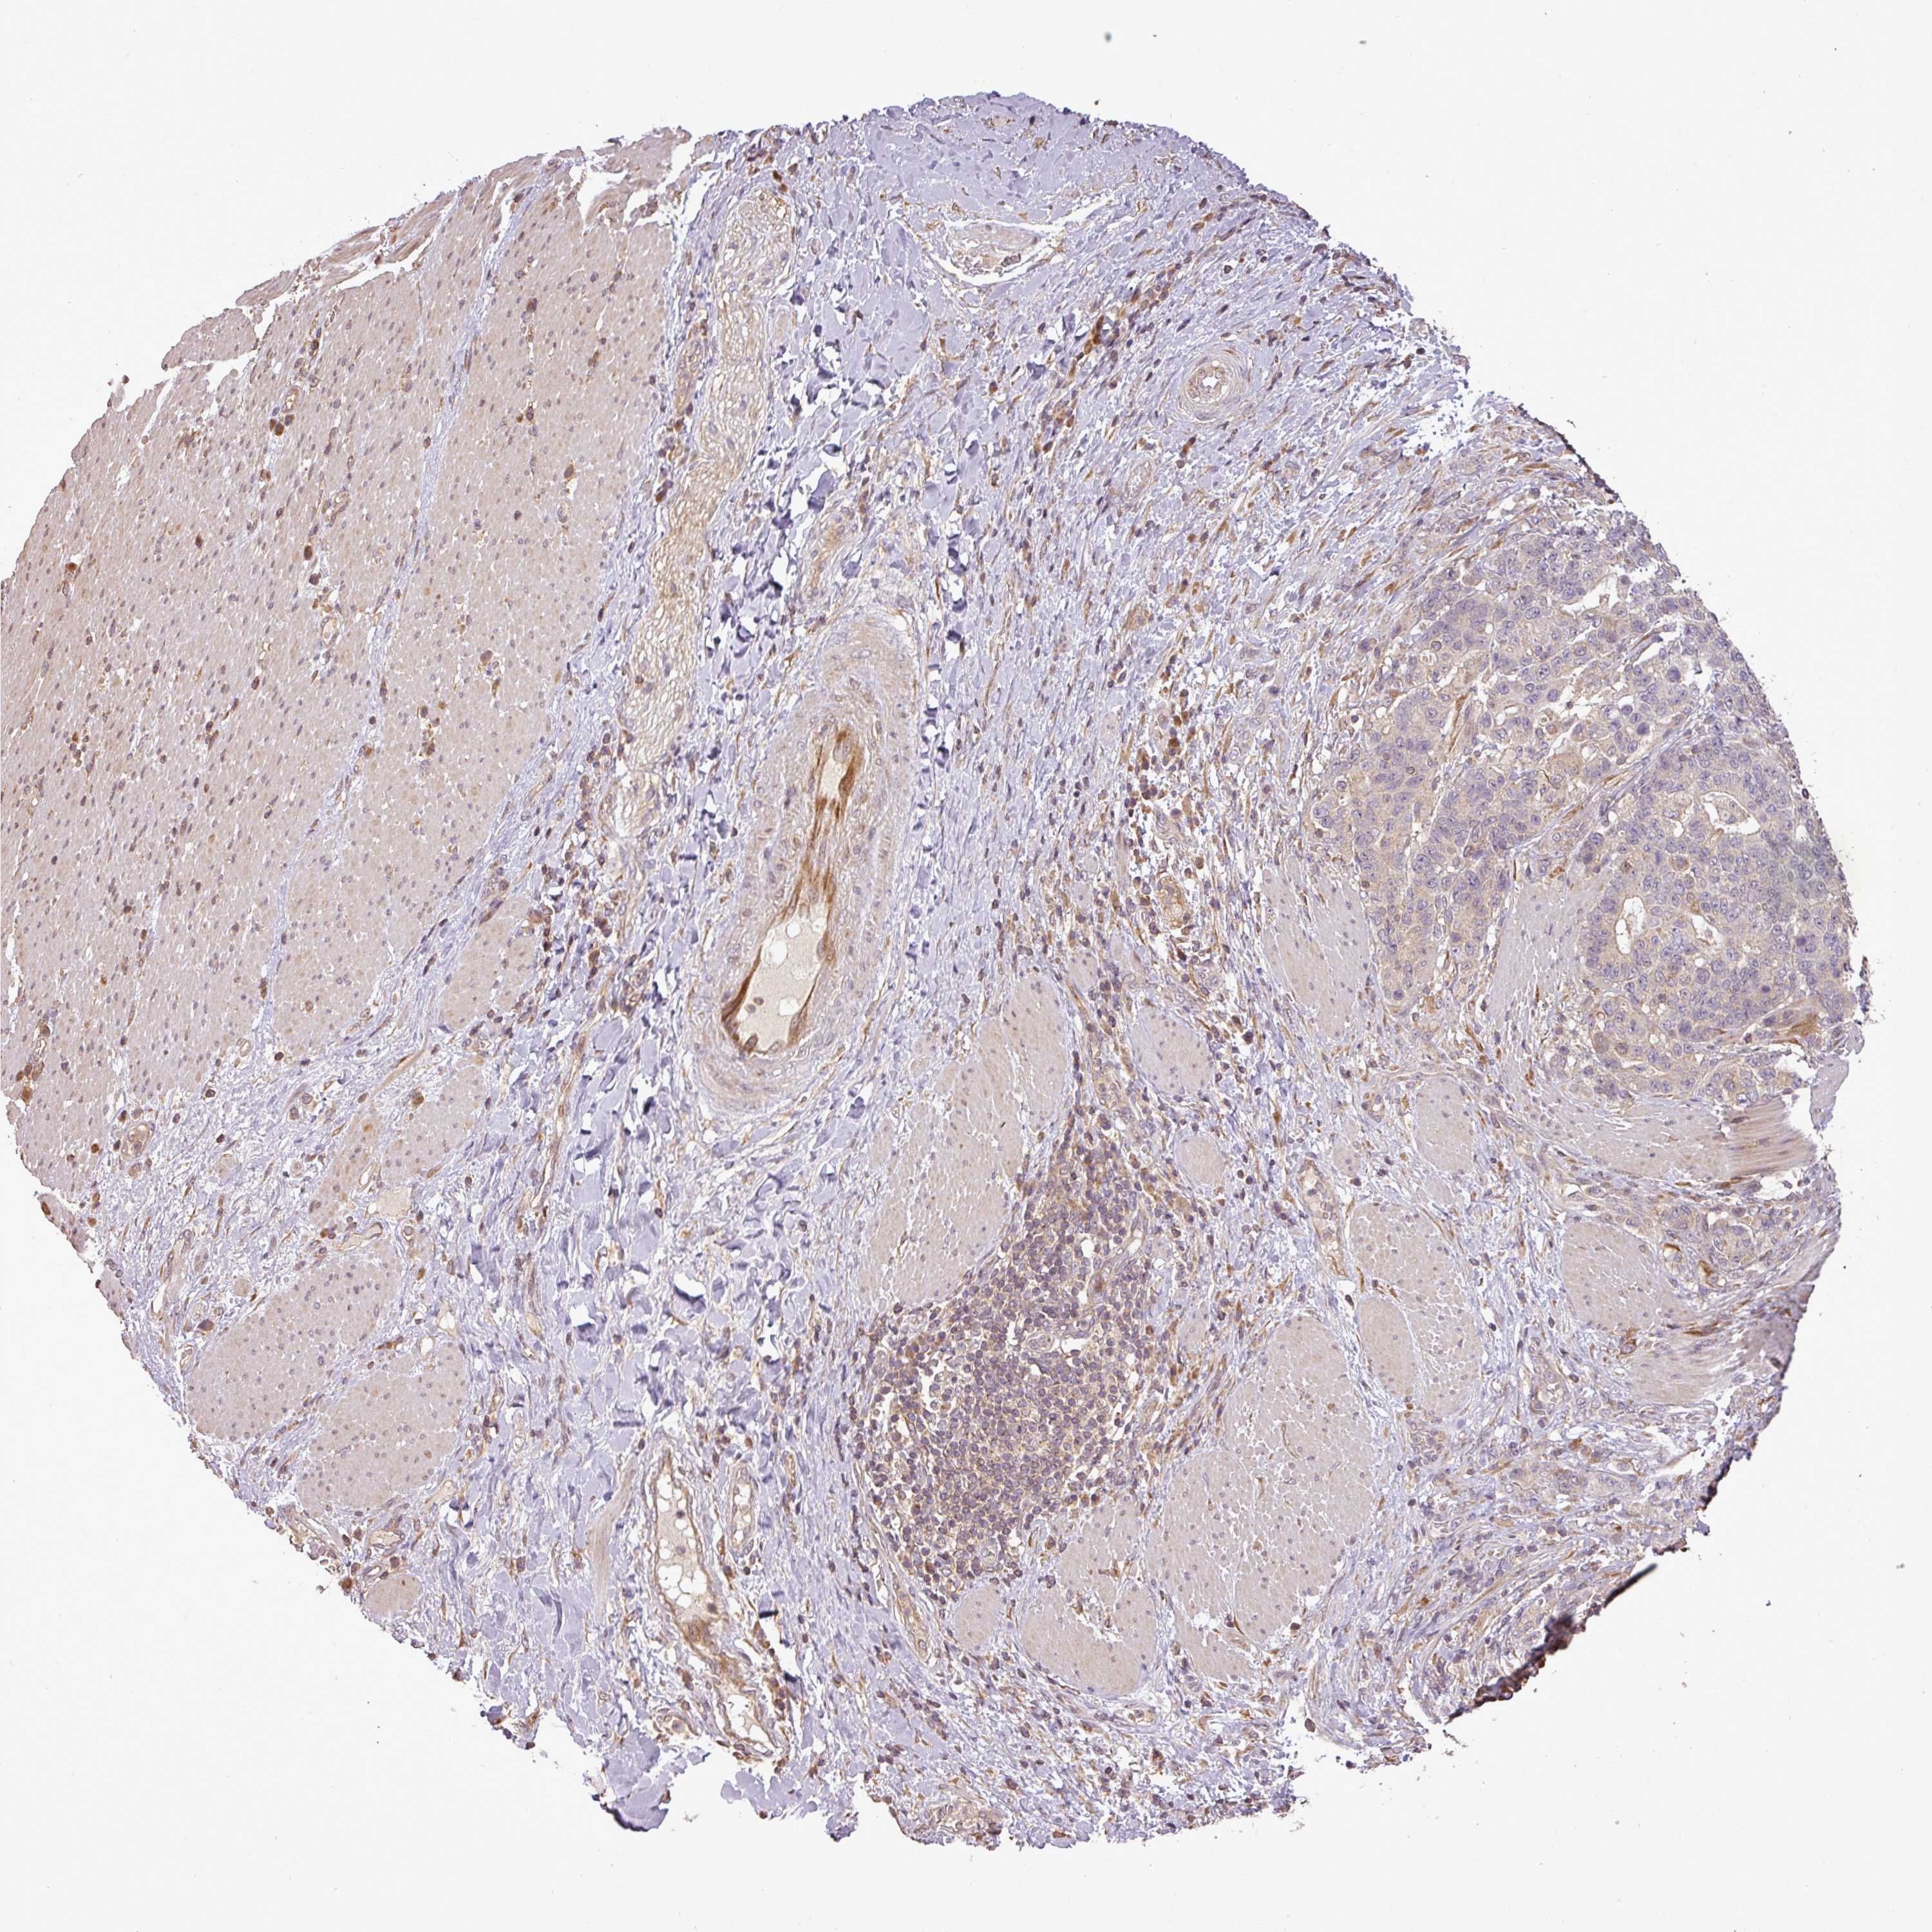

STOMACH CANCER - Protein expressioni

A mouse-over function shows sample information and annotation data. Click on an image to view it in a full screen mode. Samples can be filtered based on level of antibody staining by selecting one or several of the following categories: high, medium, low and not detected. The assay and annotation is described here.

Note that samples used for immunohistochemistry by the Human Protein Atlas do not correspond to samples in the TCGA dataset.

Antibody stainingi

Antibody staining in the annotated cell types in the current human tissue is reported as not detected, low, medium, or high, based on conventional immunohistochemistry profiling in selected tissues. This score is based on the combination of the staining intensity and fraction of stained cells.

Each image is clickable and will lead to virtual microscopy that enables deeper exploration of all samples and also displays staining intensity scores, fraction scores and subcellular localization as well as patient and tissue information for each sample.

Antibody HPA042440

Antibody HPA052209

Staining

High

Medium

Low

Not detected

Intensity

Strong

Moderate

Weak

Negative

Quantity

>75%

75%-25%

<25%

None

Location

Nuclear

Cytoplasmic/membranous

Cytoplasmic/membranous,nuclear

Adenocarcinoma, NOS